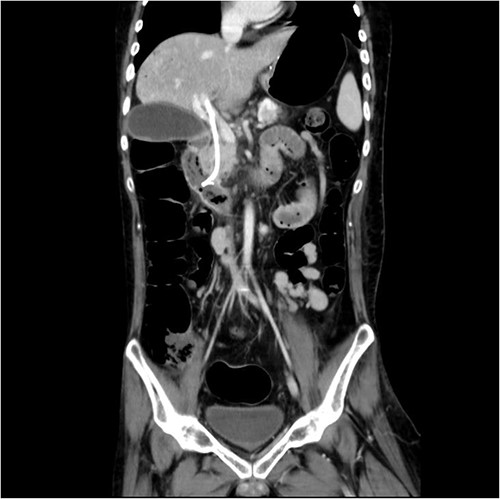

And then, a 7 French bostone scientific plastic stent was inserted over the guide wire for bile diversion. However, hemobilia was noted to be draining out from the stent right after. After reviewing the image, we realised that PVC was probably made (Fig. 3). After discussing with the general surgeon, we decided to arrange immediate surgical exploration to check for collateral damage and remove the CBD stones for cholangitis resolution. The stent was thus left inside for surgical guidance. Before the surgery, abdomen computed tomography (CT) was done and revealed retained contrast medium in the bile duct (Fig. 4) and malposition of the CBD internal stent with upper portion in the main portal vein (Fig. 5).

Just after ERCP, the abdominal CT showed retained contrast medium in bile duct.

Malposition of the CBD internal stent with upper portion in main portal vein.